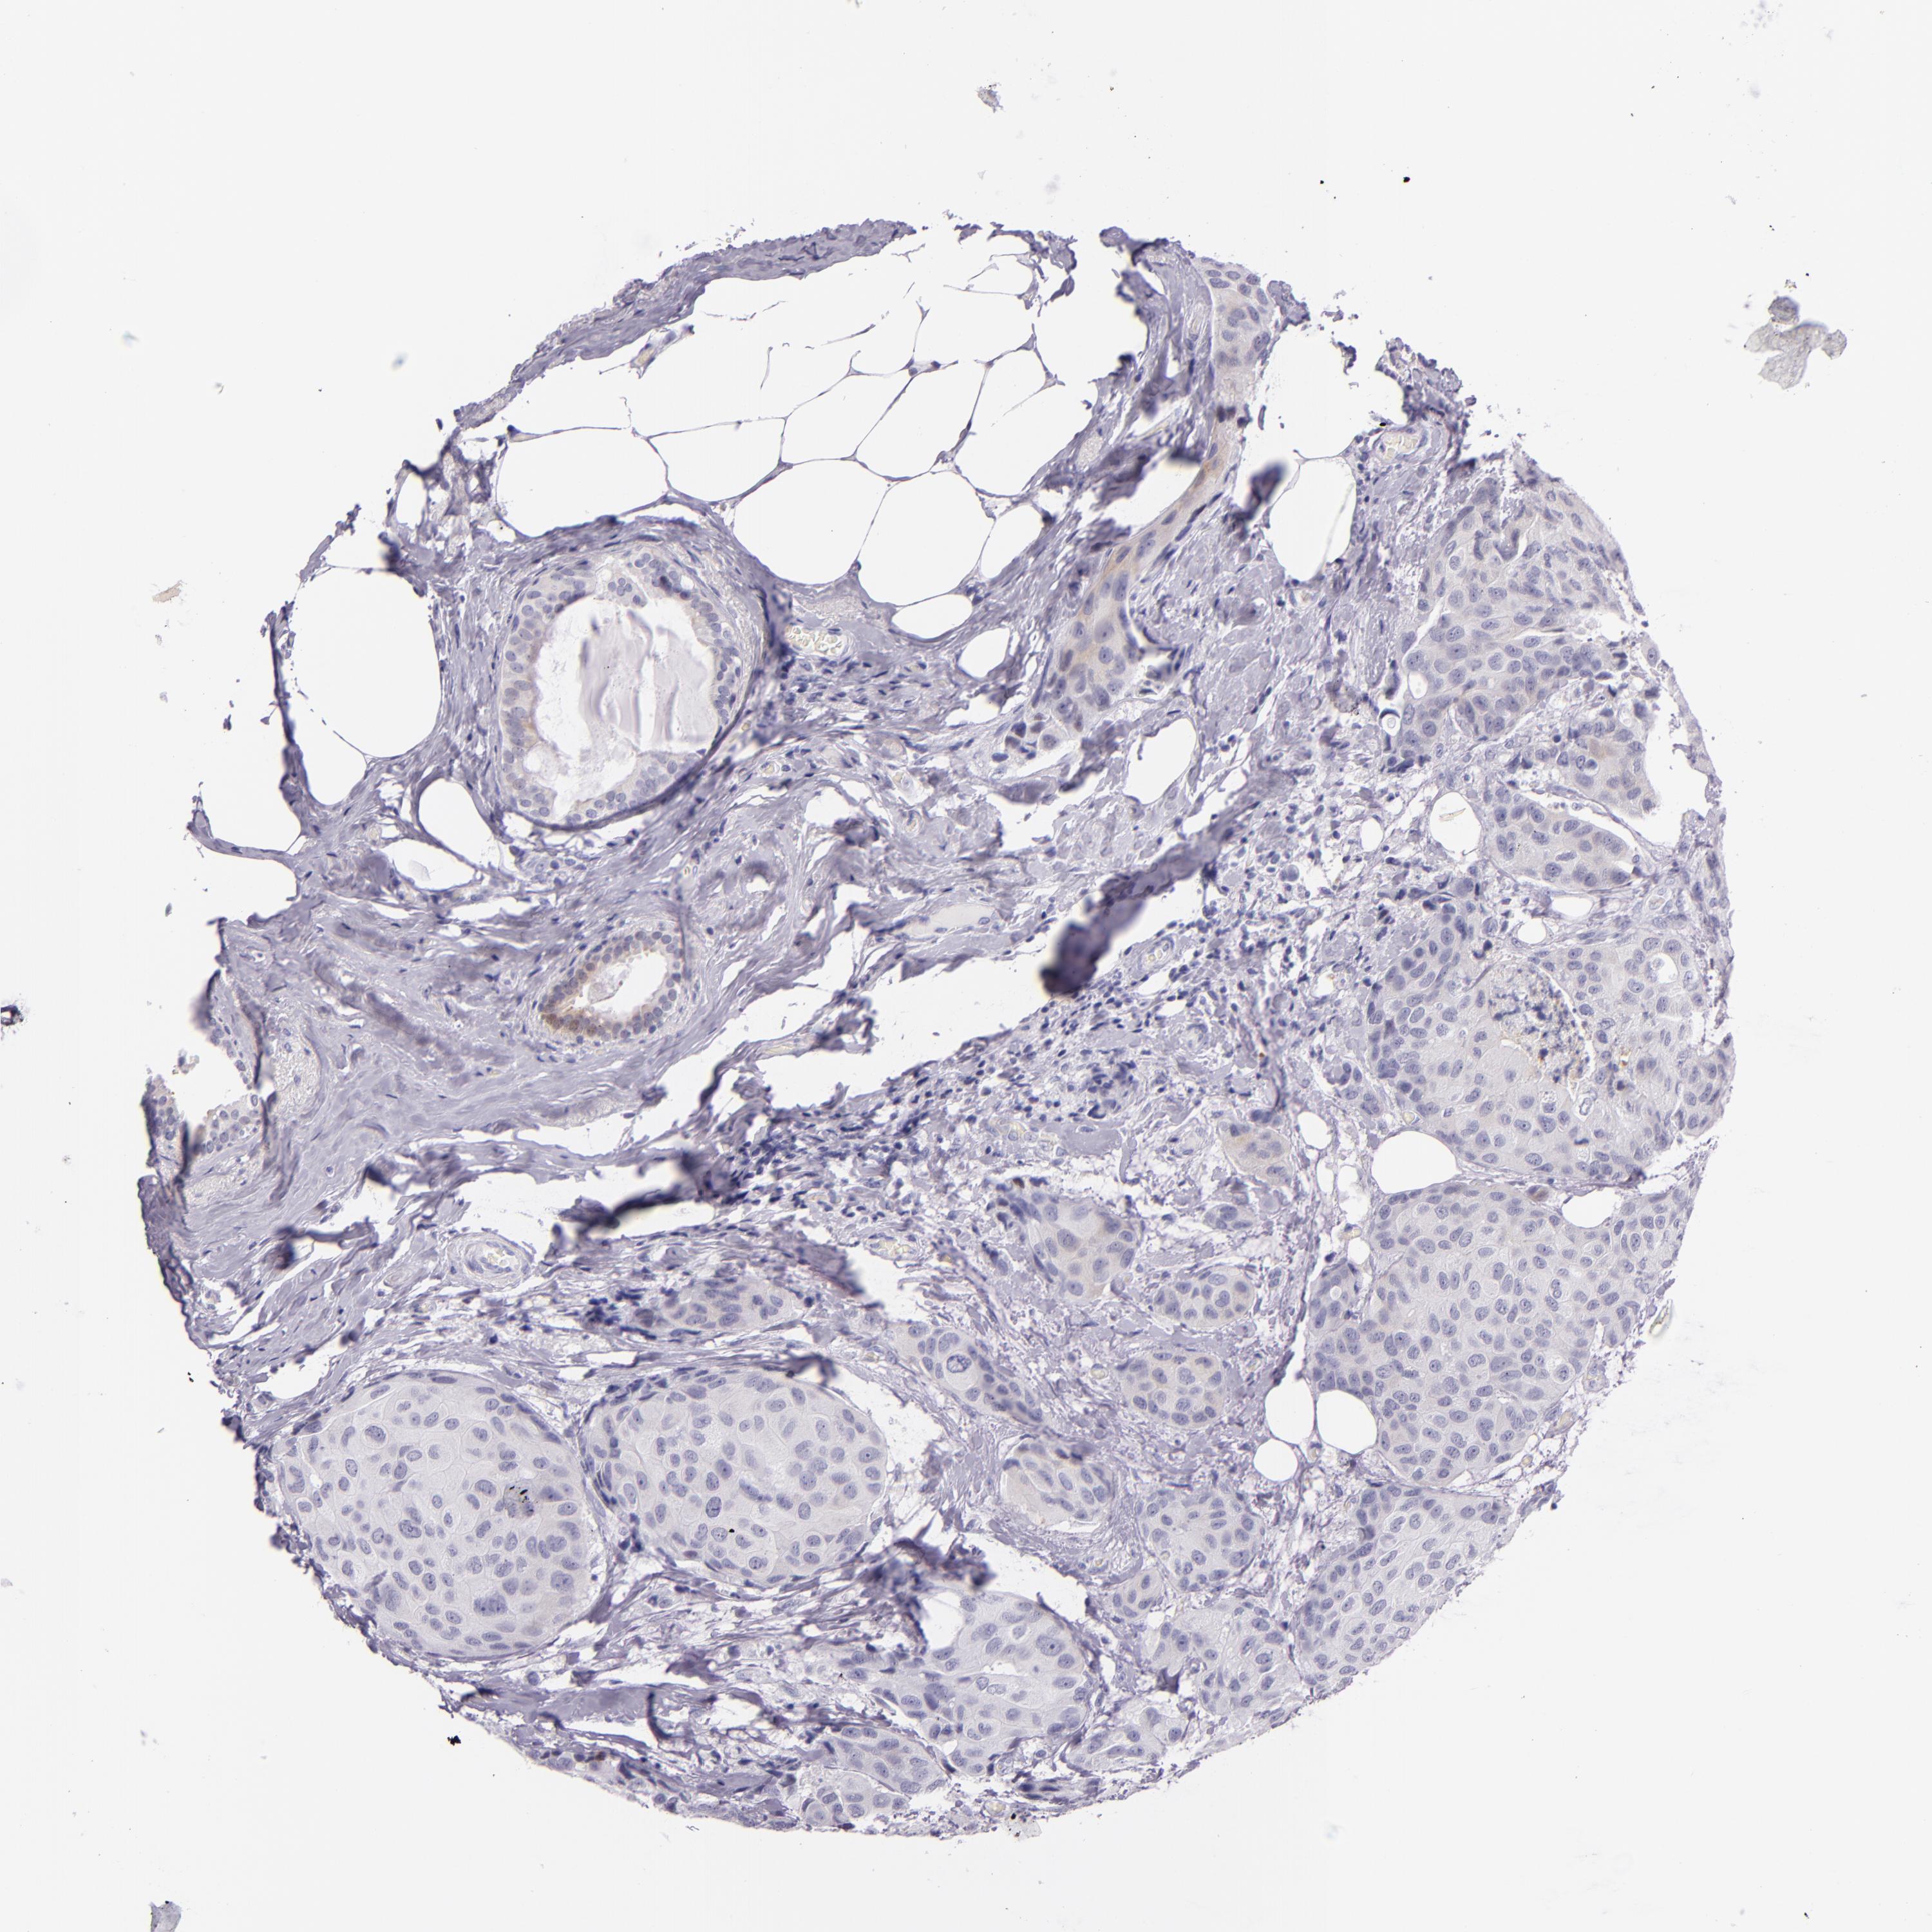

CANCER BREAST CANCER Show tissue menu

BRCA TCGA BRCA VALIDATION PROTEIN EXPRESSION

Breast cancer

Human cancer